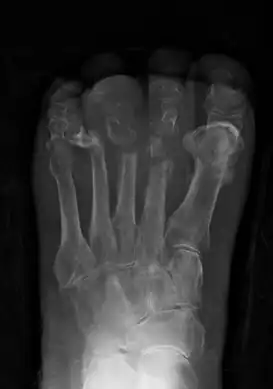

| Osteomyelitis of the base of the 1st toe | |

Extensive osteomyelitis of the forefoot -